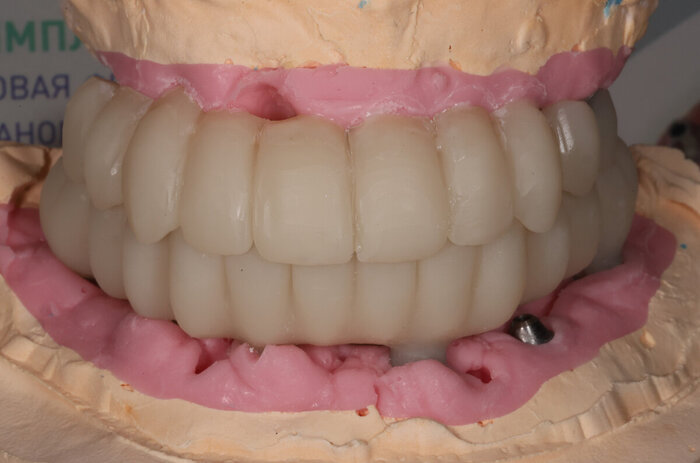

Вот как выглядит цифровая принтованная постановка:

Цифровая принтованная постановка

Разница - в первом варианте зубы не из стандартного набора, а те, что пациенту подходят больше. С этим прототипом можно даже пожить какое-то время, попривыкать к нему. Понять, что нравится, а что не особо.